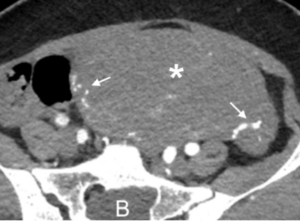

Hình ảnh trước mổ: A – Phồng gốc động mạch chủ (1), tắc hoàn toàn động mạch cảnh trái (2), đường lóc dọc theo động mạch chủ xuống (3); B – Tử cung kích thước lớn (hoa thị) với mạch máu tăng sinh (mũi tên).

Người bệnh Trần.T.C, 33 tuổi khởi phát bệnh động mạch chủ phức tạp ngay sau đẻ chỉ 1 ngày với triệu chứng đau ngực trái dữ dội lan sau lưng và lên cổ. Khi vào viện được điều trị tích cực, mức độ đau tuy có giảm nhưng vẫn còn đau nhiều kèm khó thở nhẹ. Hình ảnh siêu âm tim và chụp cắt lớp vi tính cho lóc động mạch chủ loại A cấp, dịch máu khoang màng tim, phồng gốc, hở van động mạch chủ, tắc động mạch cảnh trong trái, chênh lệch nhiều huyết áp tứ chi. Tử cung kích thước lớn, tăng sinh mạch máu nhiều (sau đẻ ngày thứ hai).